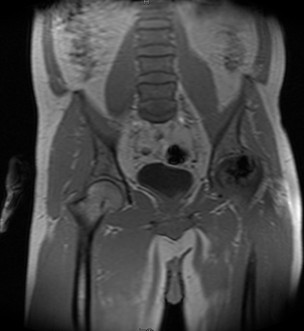

查体:左髋外侧可见一约25cm手术瘢痕,其上可见一点状结痂,左腿较右腿短缩,左腿肌肉较右腿萎缩,步态异常。左髋部无压痛,左腿外侧感觉异常,以左膝外侧为重,左髋外侧叩击痛,左足背动脉搏动未扪及异常。左下肢较右下肢短缩约2cm,左髋关节活动受限,其余各关节未见明显异常。 辅查:MRI示左股骨头坏死

诊断:左股骨头股骨颈粉碎性骨折切开复位内固定术后坏死 治疗:择期行关节置换术

股骨头坏死是一个病理演变过程,初始发生在股骨头的负重区,应力作用下坏死骨骨小梁结构发生损伤即显微骨折以及随后针对损伤骨组织的修复过程。造成骨坏死的原因不消除,修复不完善,损伤-修复的过程继续,导致股骨头结构改变、股骨头塌陷、变形,关节炎症,功能障碍。